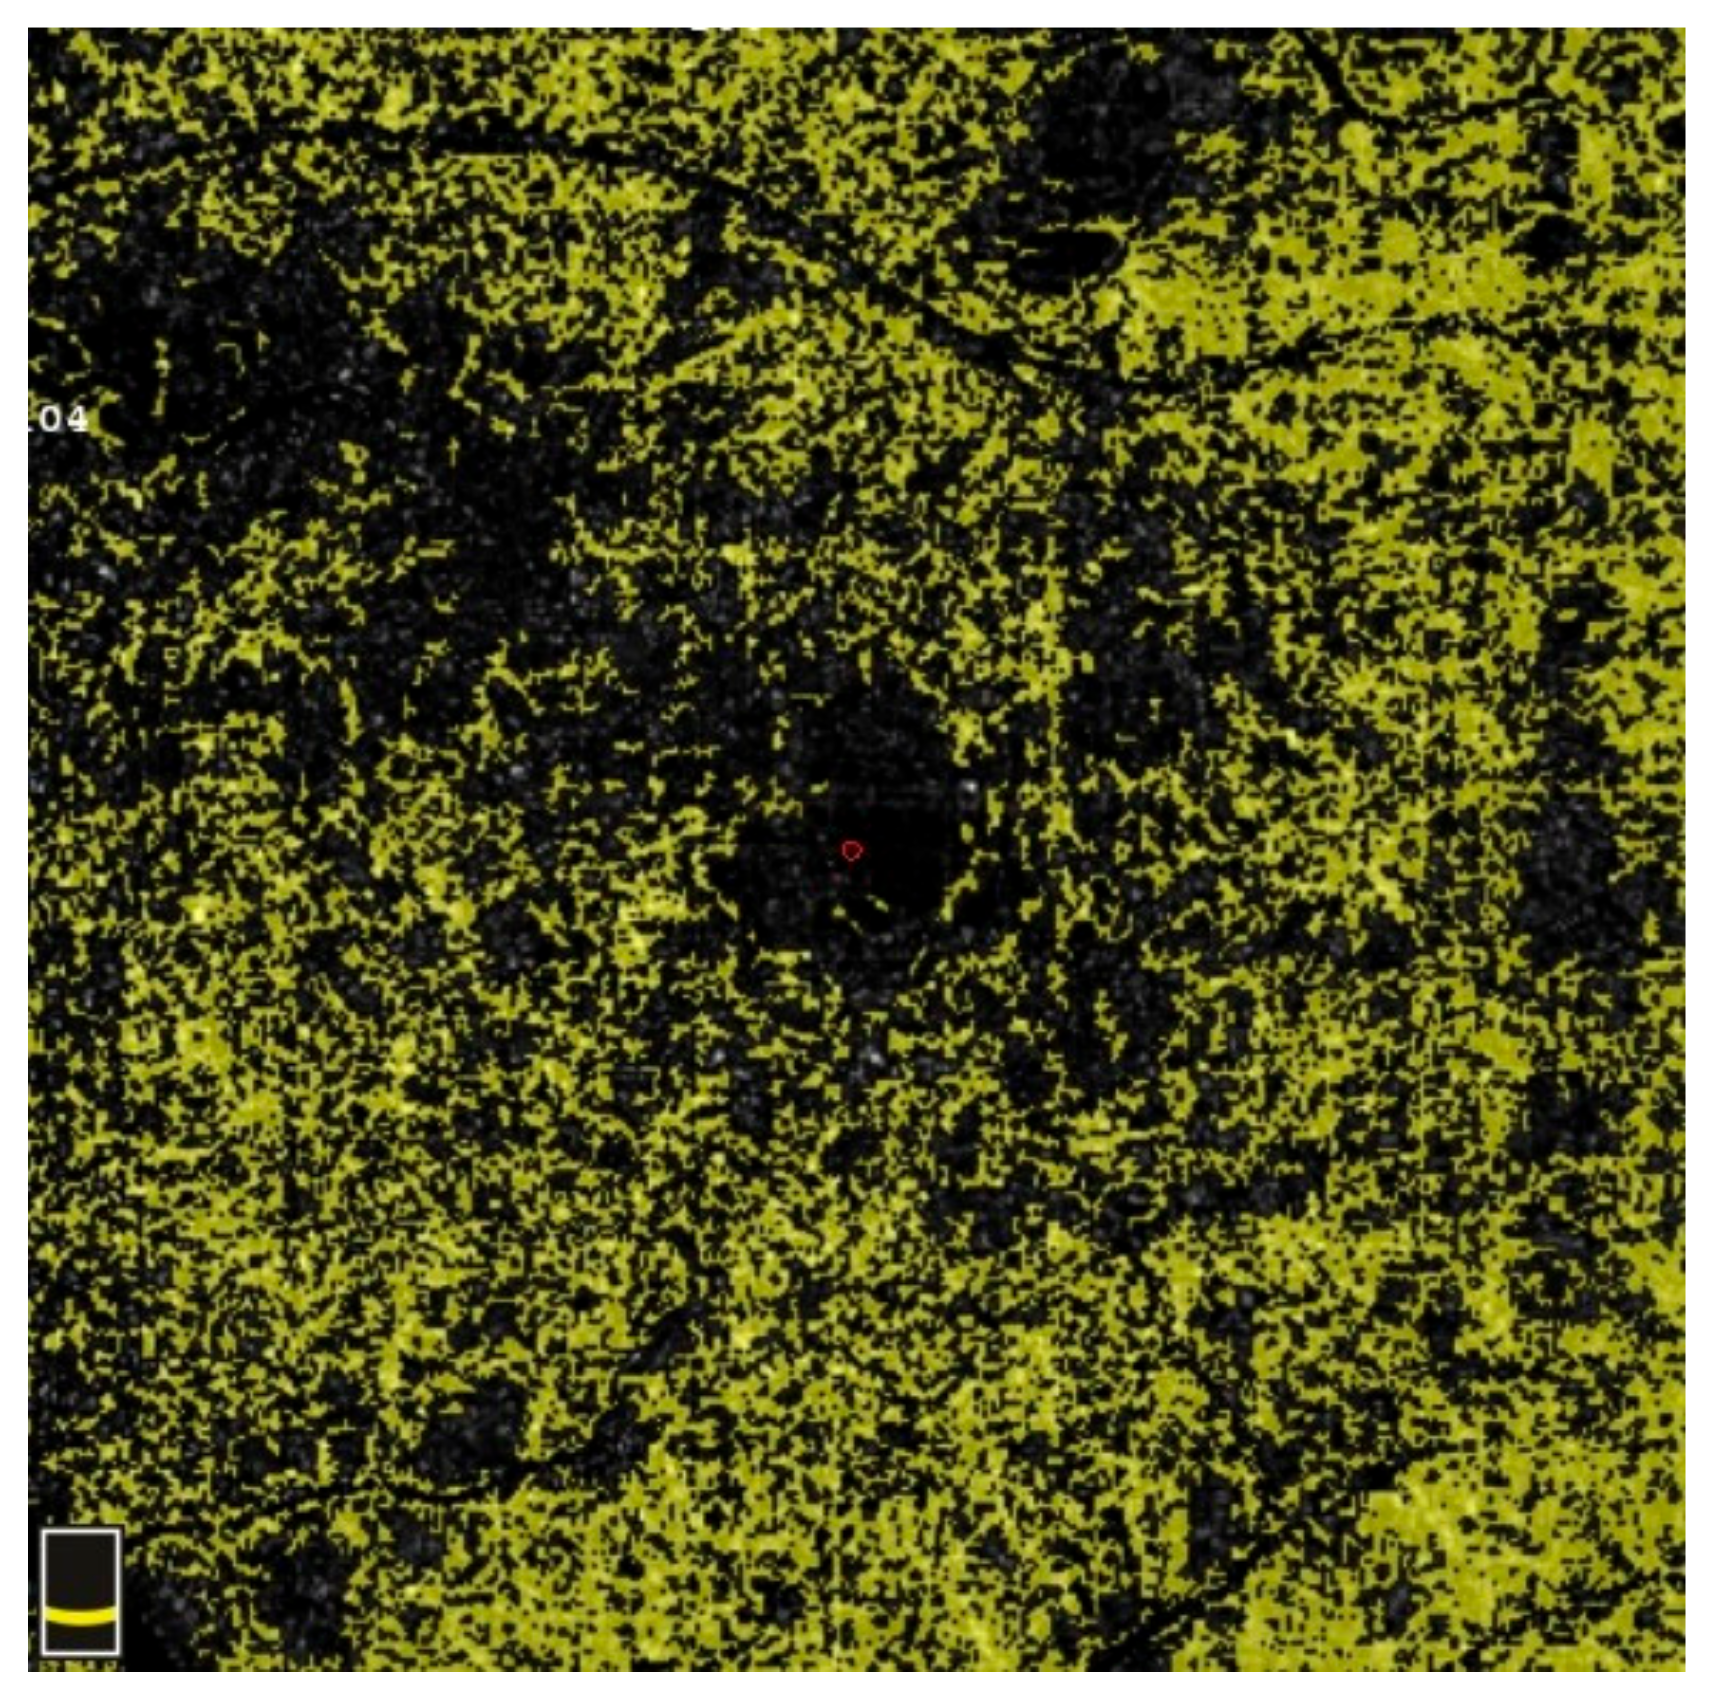

7. Examples of OCT-A Scans before and after Treatment